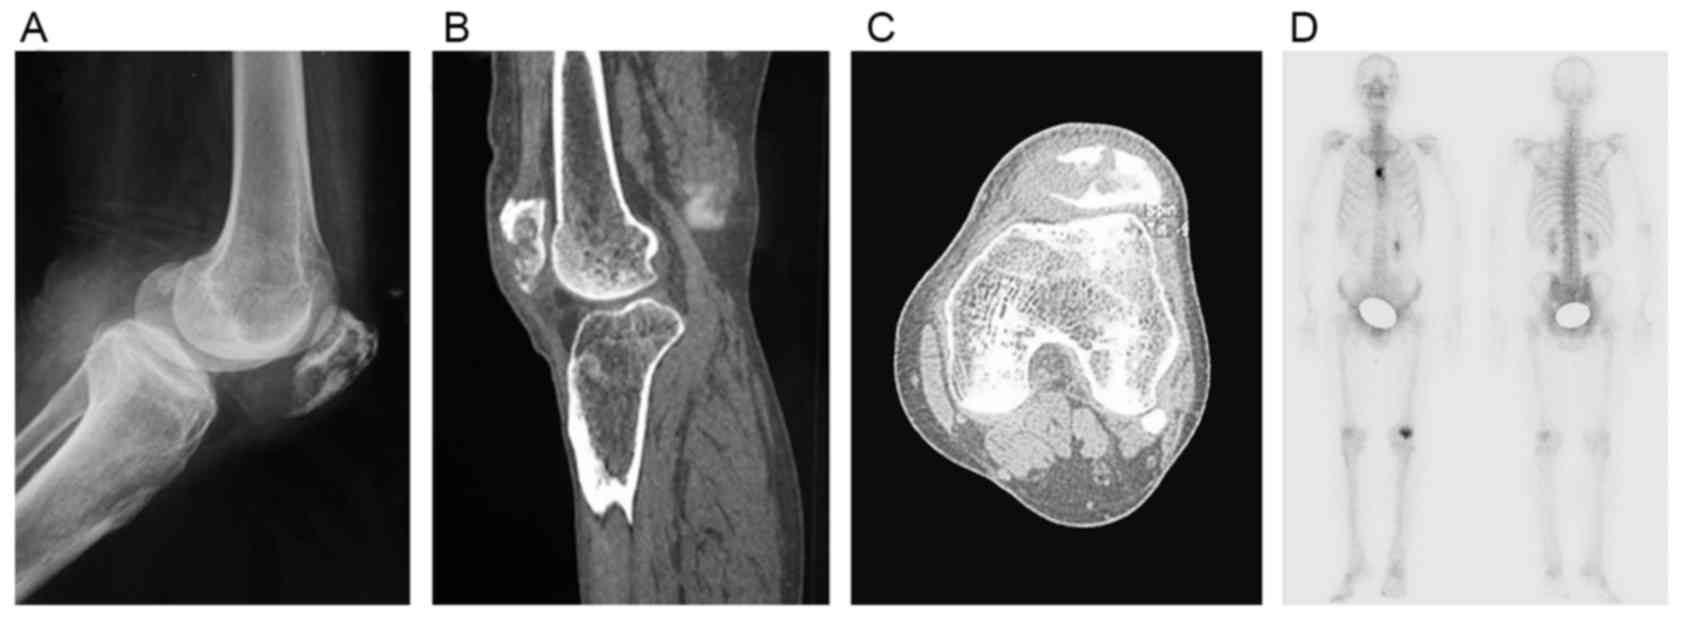

Patellar metastasis from primary tumor (Review)

Although bone tumors are frequently located in the knee area, primary tumors of the patella are rare and patellar metastases are even rarer. Knee pain is the most common complaint of patients with patellar metastases. Owing to the low incidence of patellar metastases, misdiagnosis is not unusual. The present review analyzes ~44 cases of patellar metastases originating from distinct primary sites. Reports of malignant tumors of the lung and kidney metastasizing to the patella were more common than those of other patellar metastases. Relative incidence, symptomatology, imaging features, histopathology and treatment options for these patellar metastatic lesions are described respectively along with a review of the literature. Despite numerous experiments demonstrating the reasons for implantation of tumor in patella, the answer to this question has not yet been revealed. In the light of the increasing attention on the diagnosis and the treatment of these lesions, the availability of the integrated information regarding metastases in the patella becomes more relevant.

Figure 1